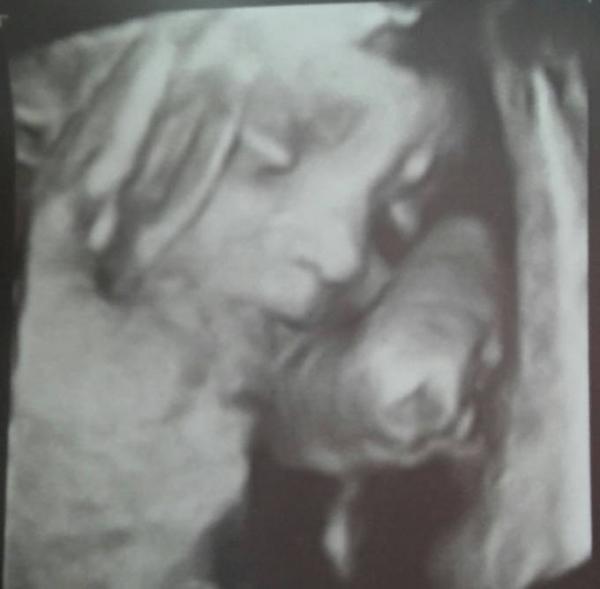

Jetzt bin ich mal dran mit Baby Präsentation. Hab dieses Foto geschenkt bekommen beim letzten US in der 25ssw und bin geschmolzen vor Liebe...

Meine Nase und Papas Augenform

Lg Sarah + Fabienne